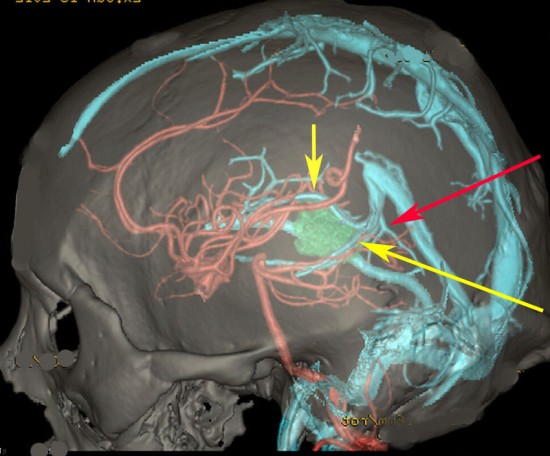

松果体腫瘍へのOTAのルートです。occipital transtentorial apporachというのは黄色の矢印に沿ってガレン大静脈の下に入る方法であり,そこから松果体部を通って第3脳室内へ直線的な視野が展開します。

一方,赤の矢印に沿ったルートは parieto-occipital transtentorial approachです。このルートでは内大脳静脈 internal cerebral veins を見ることがかなり難しいです。更に,第3脳室に入るためには脳梁膨大部 spleniumを切断する必用があります。ただし,小脳上部や第4脳室を見るときにはparietal寄りのルートを使います。

この2つのルートを混同している脳外科の先生はとても多いと思います。OTAとは,外後頭隆起を削除して,後頭極(後頭葉)を牽引して,テントの全長を切開しなければ遂行できない到達法であることを認識して下さい。